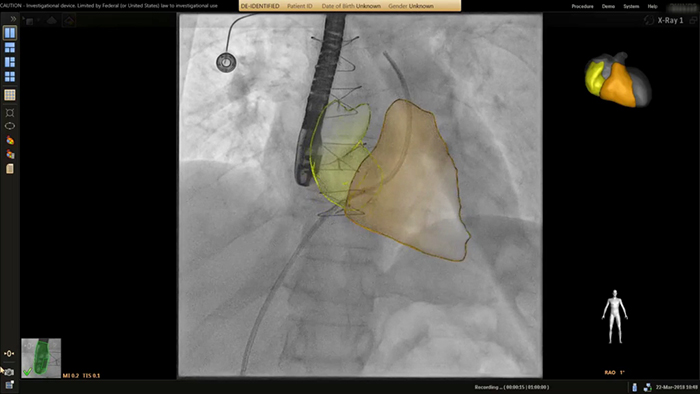

Anatomical landing zone marking on TSM Pro

SmartCT live guidance